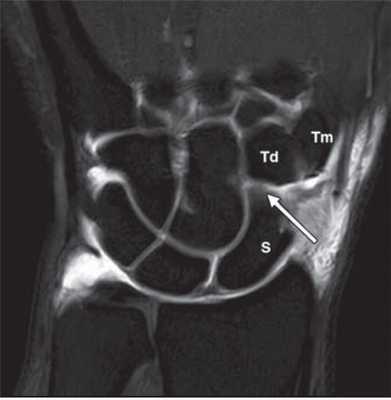

МРТ кисти. Корональная Т1-взвешенная томограмма с подавлением сигнала от жира. Ладьевидно-трапецевидная связка в норме. Обозначения: S- ладьевидная кость, Td - трапециевидная кость, Tm - трапеция.